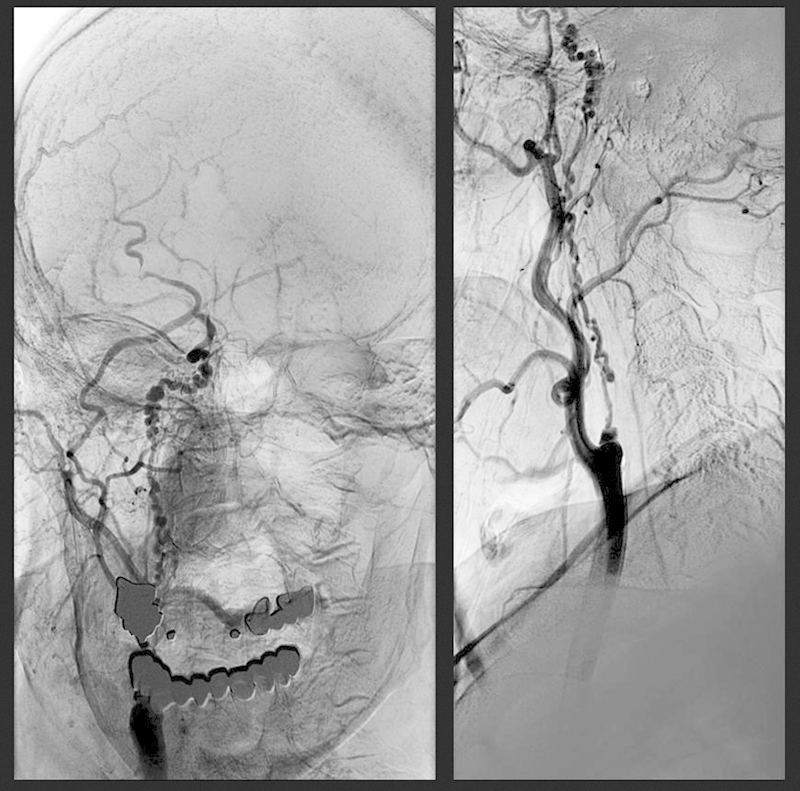

A 75-year-old asymptomatic patient, with a low cardiovascular risk, underwent ultrasonography of the carotid arteries because of a murmur along the right carotid artery. A stenosis of the right internal carotid artery (RICA) was diagnosed. Carotid angiogram revealed a long stenosis of RICA spreading from the origin of the artery with the typical “string-of-beads” sign that is characteristic for FMD consisting of alternative areas of narrowing and dilation (Fig. 1).1 As the patient was asymptomatic and efficient brain circulation was provided by collaterals, conservative therapy was chosen with a favorable 4-year follow-up.

Fig. 1.

Angiography of the right carotid artery. Medial fibromuscular dysplasia of right internal carotid artery with the typical “string-of-beads” sign. Diameter of the “beading” is larger than the diameter of the affected artery which is typical for medial fibroplasia. In perimedial fibroplasia, the diameter of the “beading” is generally smaller than the diameter of the artery involved.